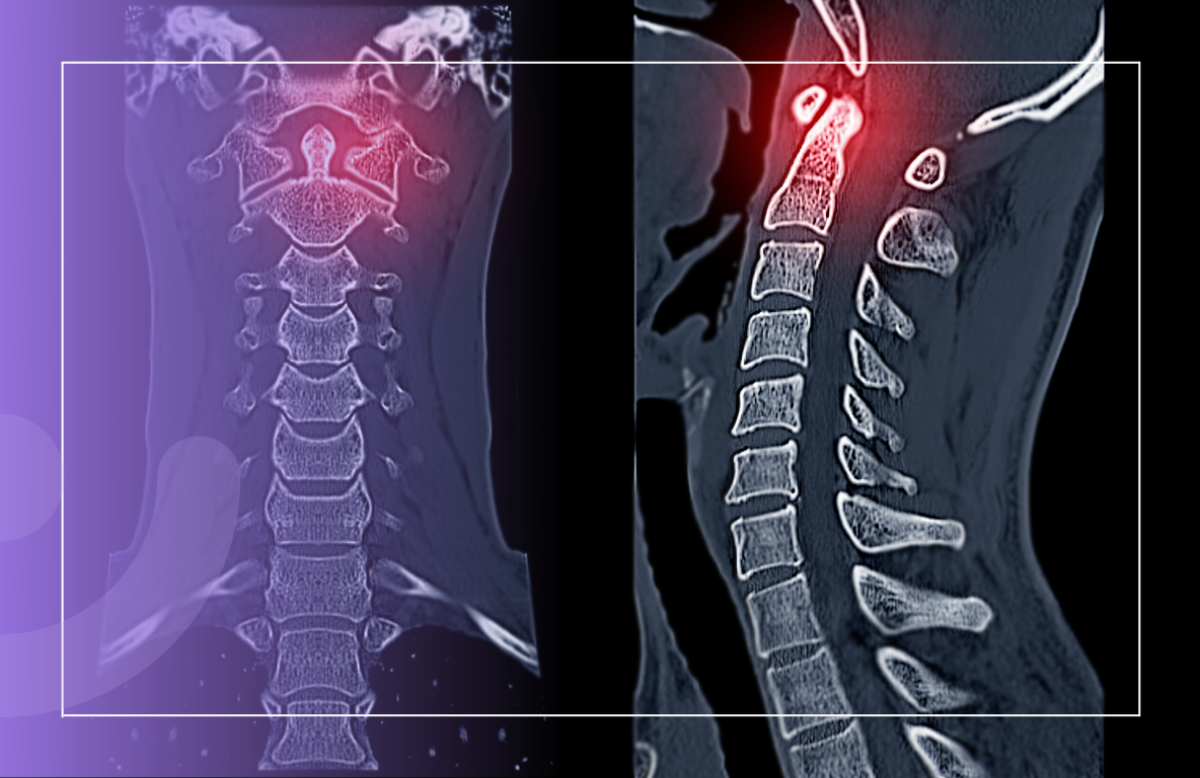

Хвороба Бехтерєва, відома також як анкілозуючий спондиліт, — це захворювання, яке змушує питати себе: що робити, коли тіло ніби відмовляється тебе слухатися?

Фундаментальність цієї недуги полягає в ураженні осьового скелета. Уявляйте: хребет, який перетворюється на нерухомий стовп. Немає гіршого відчуття, ніж безпомічність. Без стабільності в тілі важко знайти її в житті.